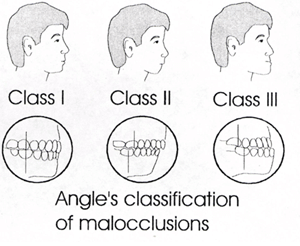

La première classification a été établie par Angle, et c’est celle que les dentistes utilisent encore aujourd’hui. Angle a divisé les malocclusions en trois classes. La classification est basée sur la position sagittale des dents et des mâchoires.

La classe 1 comprend tous les cas où il y a une neutrocclusion. Ces patients ont une relation sagittale normale entre les dents et les mâchoires, mais peuvent souffrir d'autres problèmes tels que le surpeuplement, la surocclusion, la sous-occlusion, l'espacement, etc.

La classe 2 est également appelée dystoclusion. Ces patients présentent une pathologie dans laquelle la mandibule est en position rétrograde par rapport au maxillaire.

La classe 3 est appelée malocclusion. Elle concerne les patients qui souffrent de prognathisme, c'est-à-dire que la mandibule prend une position frontale par rapport au maxillaire.

Les pathologies telles que l'encombrement, l'espacement, la sous-occlusion, l'occlusion croisée et autres ne sont pas dans la relation sagittale et ne font donc pas partie de cette classification. Différentes malocclusions peuvent être combinées dans un même cas. Ainsi, un patient peut avoir un encombrement et une dystocclusion en même temps.